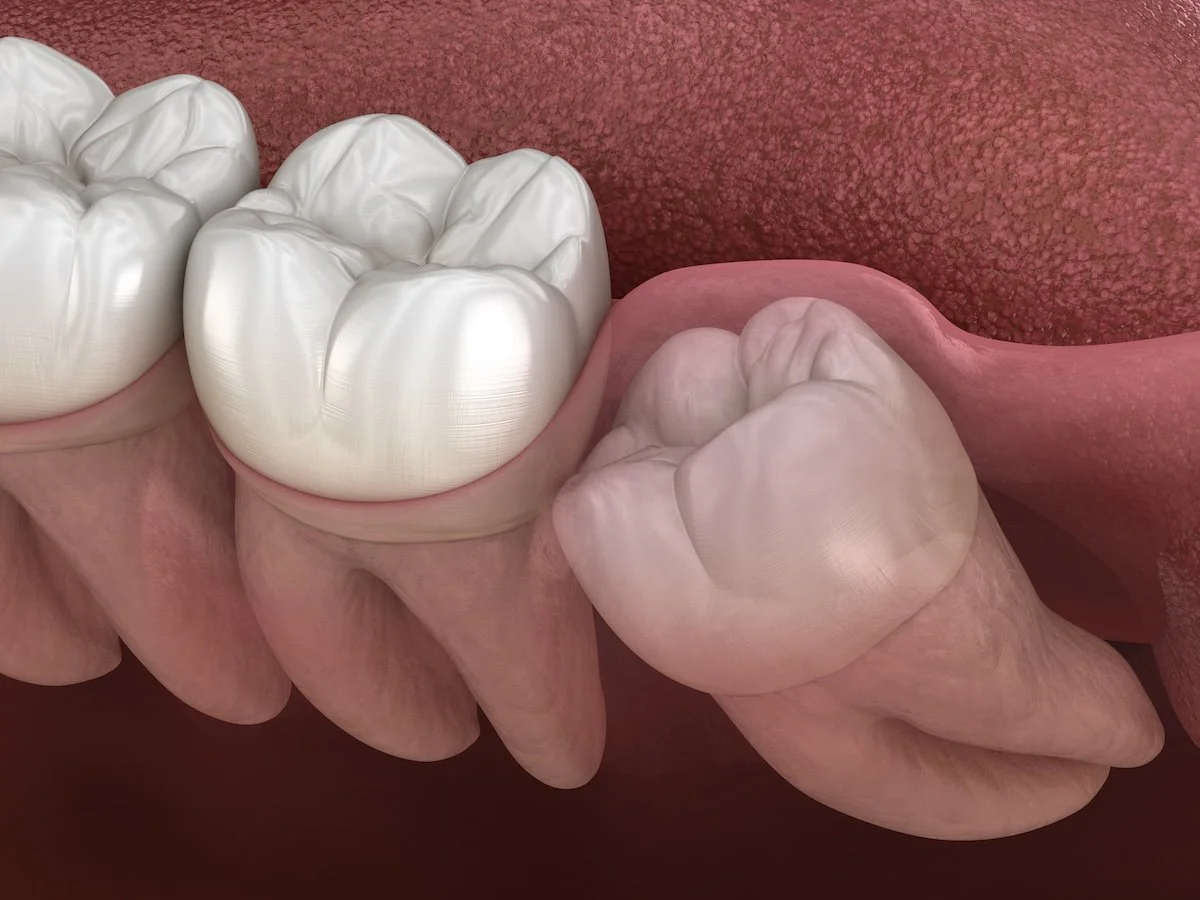

Wisdom Teeth Removal

Wisdom teeth (third molars) often erupt during the late teens or early twenties. In many cases, they can become impacted, grow at the wrong angle, or cause infections and discomfort.

At Margaret River Dental, Dr Joachim Peermamode provides:

• Careful assessment using dental X-rays

• Gentle surgical removal of impacted wisdom teeth

• Sedation and pain management options to ensure comfort